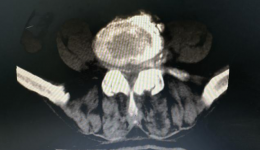

“你是否每天在电脑前工作超过6小时”“你是否经常打麻将”“你是否长年累月坐在驾驶室里开车”“你是否每天下班后就腰杆酸胀疼痛,下肢乏力麻木,就想摊在沙发上”……如果“是”,那就得注意是否有腰椎间盘突出了。为解决大家腰椎间盘突出问题,...

病例分享邱大爷90岁高龄,双侧臀部疼痛已经5年多了,疼痛的症状已经蔓延到大腿后外侧和小腿后外侧,偶而还会有腰部酸胀感、下肢无力、跛行,疼痛严重影响睡眠。反复针灸、理疗、康复……治疗,疼痛都得不到明显缓解。经熟人介绍,在家人的陪同下,...